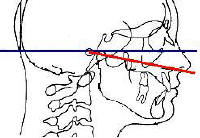

1-Ajuste el plano de oclusión de los rodetes,

utilizando la regla de Fox.

- Es recomendable conocer las

características que deben tener los rodetes.

- Introduzca el rodete superior dentro

de la boca del paciente, apoye la parte intra-oral

de la regla de Fox en la cara oclusal del rodete superior y

verifique que las alas extraorales

deben estar paralelas al plano de Camper; que es la linea

imaginaria que va desde el meato de conducto auditivo externo al ala

de la nariz.

- Verifique en el plano frontal, si el plano de

oclusión es paralelo a la línea que une las pupilas de nuestro

paciente (plano bipupilar)

Regla de Fox |

En color

rojo Plano de Camper |

En color verde línea

bipupilar |